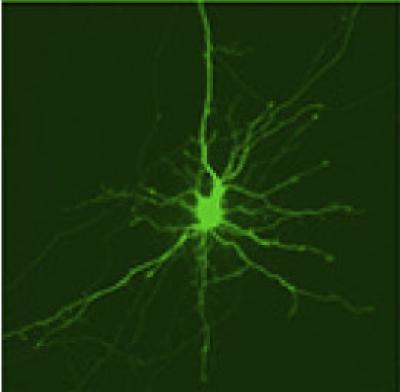

To measure how quickly proteins are cleared away from cells, the researchers developed a new technique called optical pulse-labeling, allowing them to follow specific proteins in individual living cells. To test the technique, they grew brain cells in a dish and turned on Dendra2, a photoswitchable protein that glows from green to red after being hit by a specific type of light. Both the red and green glow can be followed until the protein is cleared from the cell. In this way, the researchers could track the lifetime of newly produced Dendra2 (which glows green) and older, photoswitched Dendra2 (which glows red) until the protein was cleared away from the cell.

This is an image of a striatal neuron with activated Dendra2 protein.

(Photo Credit: Courtesy of Dr. Steven Finkbeiner, University of California, San Francisco.)